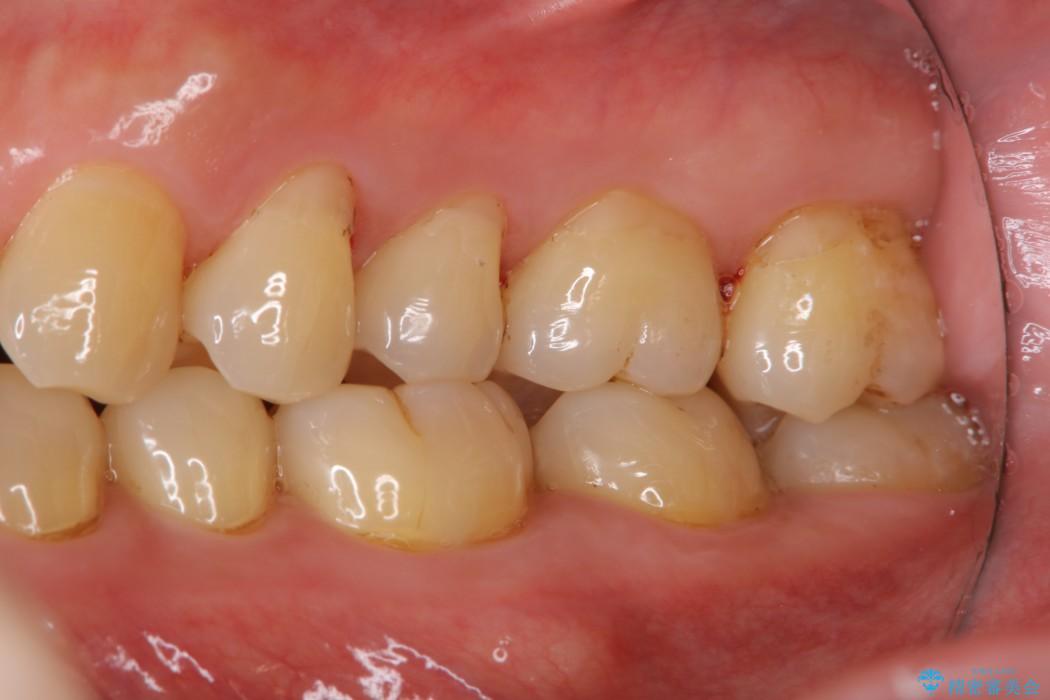

【40代男性】歯にこびりついた着色のクリーニング

堅くこびりついていたステインも1時間コースのPMTC(プロフェッショナルクリーニング)できれいな状態になりました。